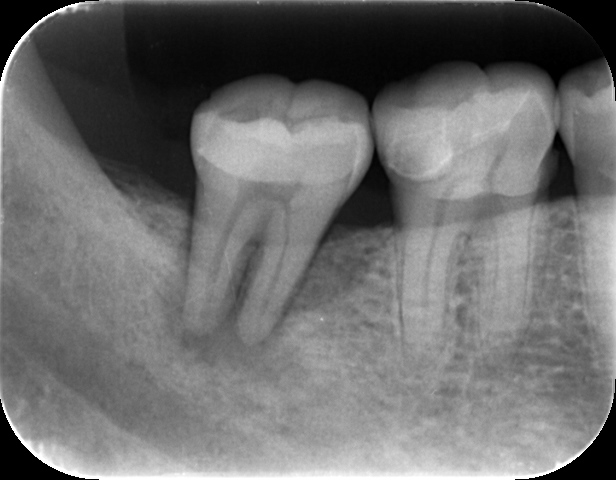

治療前のレントゲンで根の先が黒く写っています。これは歯の中の神経が壊死してしまい感染を起こしています。

既に根管治療を受けている歯でも、根管内が汚れていると同様に膿が溜まってしまいます。